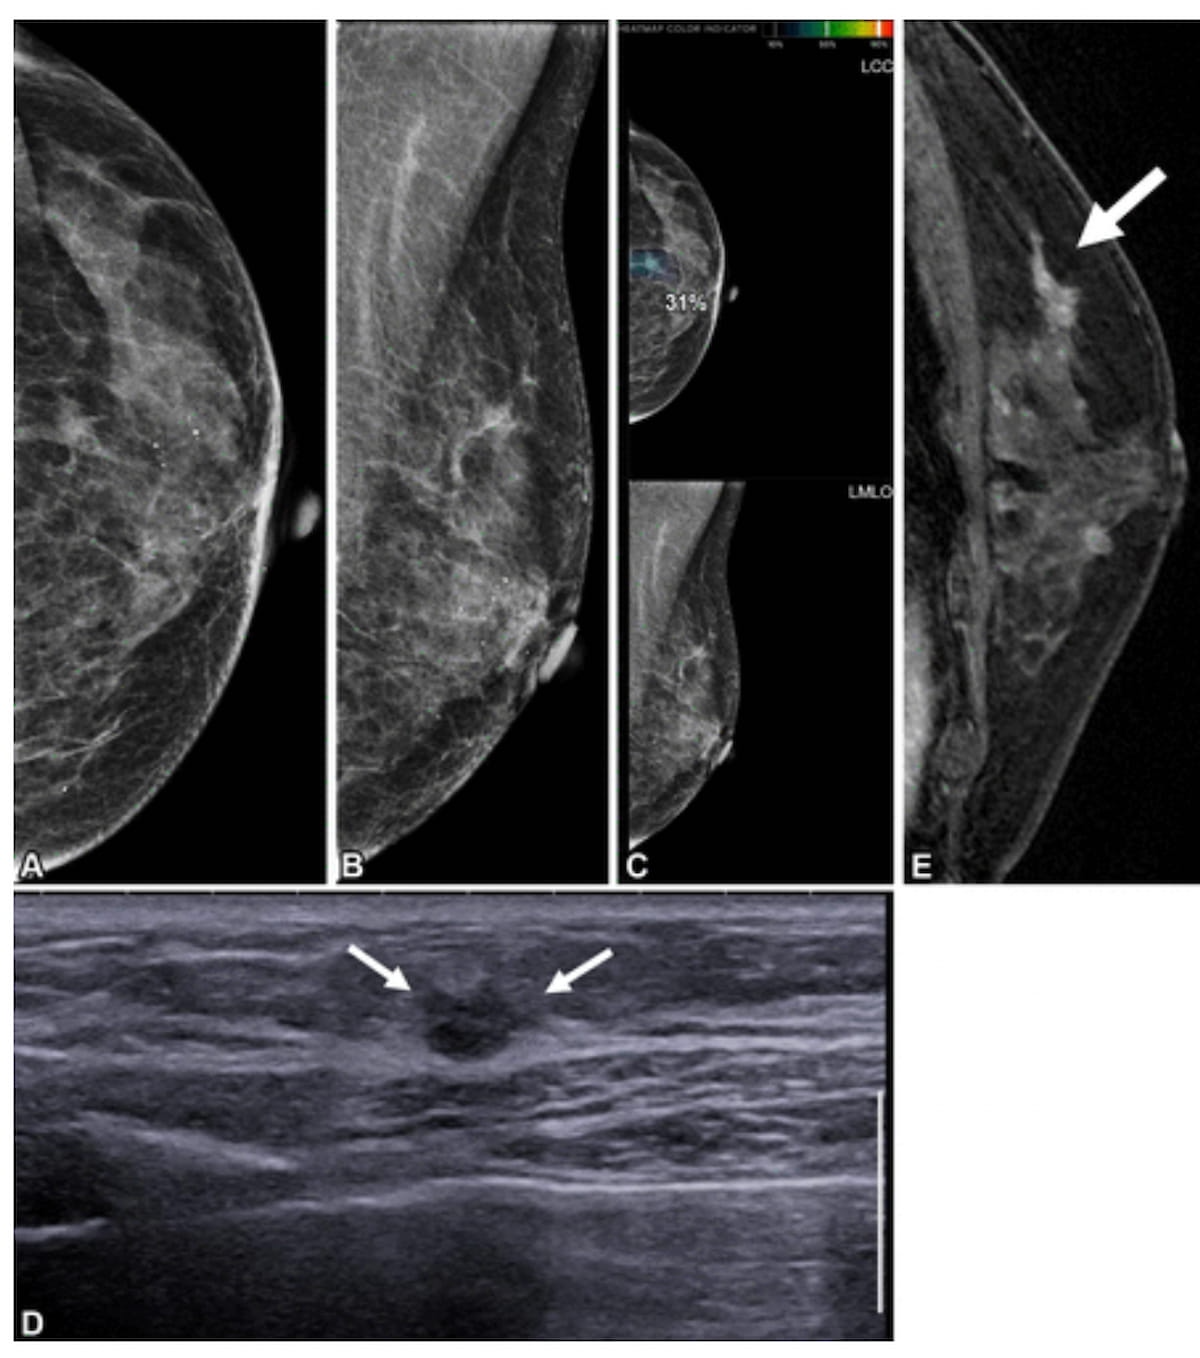

Here one can see mammograms (A and B), artificial intelligence (AI) mammogram assessment (C), supplemental ultrasound (D) and preoperative contrast-enhanced sagittal T1-weighted MRI (E) for a 65-year-old woman who had contralateral second breast cancer 6.3 years after undergoing a right mastectomy. While the initial mammograms were deemed benign, there was an AI score of 31 for a lesion on a craniocaudal mammogram. Supplemental ultrasound and preoperative MRI revealed a lesion that was subsequently diagnosed as ductal carcinoma in situ. (Images courtesy of Radiology.)